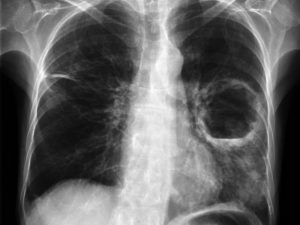

Рентгенография легких является наиболее достоверным исследованием для постановки диагноза, а так же для дифференциации абсцесса от других бронхолегочных заболеваний. В сложных диагностических случаях проводят КТ или МРТ легких. ЭКГ, спирография и бронхоскопия назначаются для подтверждения или исключения осложнений абсцесса легкого.

- При проведении рентгена и на КТ можно увидеть образование воспалительного инфильтрата, который характеризуется гомогенным затемнением. Если абсцесс прорывается в область бронхиального дерева, то обнаруживается гнойная мокрота в большом количестве, которая имеет неприятный запах, иногда имеется примесь крови.

- Чаще всего при прорыве абсцесса наблюдается облегчение состояния пациента, температура начинает понижаться. При этом на рентгене можно увидеть, что в легких образуется просветление. Большое значение имеет состояние пациента, развитие заболевания, а также данные, которые были получены в результате лабораторных, функциональных, иммунологических и рентгенологических исследований.

- на рентгеновском снимке легких видна тень округлой формы;

- рентген показывает округлую полость и на снимке можно увидеть уровень мокроты в ней.

Основной инструмент диагностики абсцесса легкого – рентгенография

Основной инструмент диагностики абсцесса легкого – рентгенография. Она позволяет выявить очаги воспаления, определить их размер и локализацию. Компьютерная томография обычно не проводится. Она нужна, если рентген не показал четкую картину, или есть необходимость исключить другие патологии.